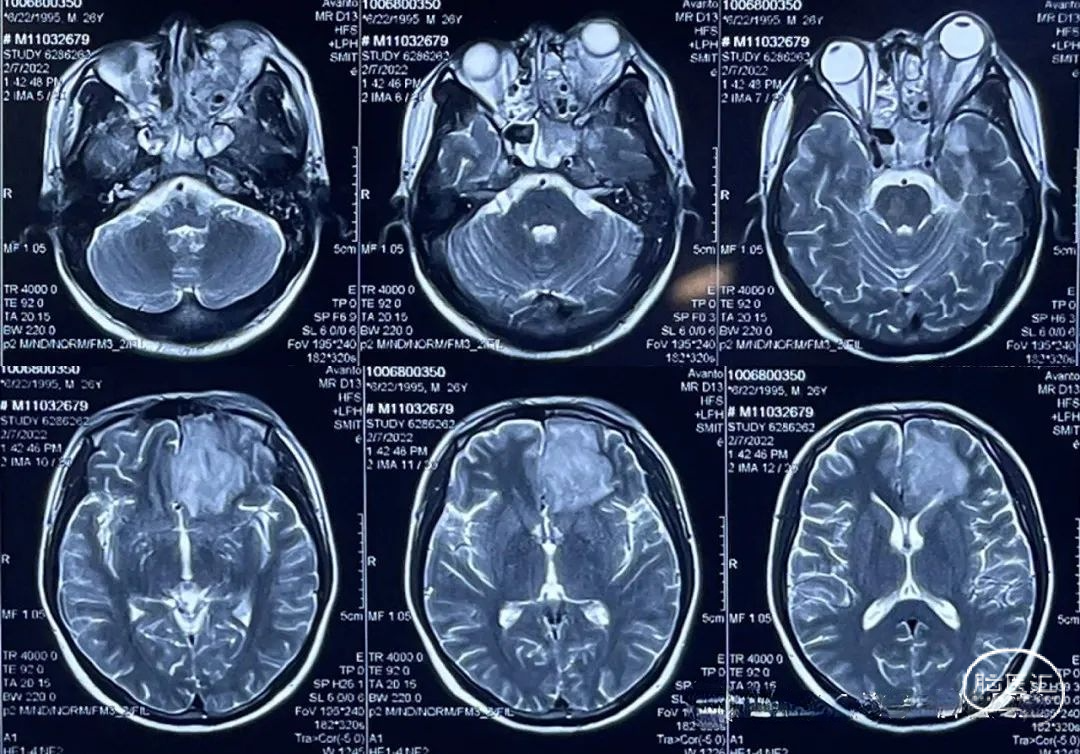

2022.02.07 MR:鼻腔,眼眶内呈现术后改变,额叶水肿范围逐渐局限。

2022.03.02 MR/CT:左侧额叶脓肿形成,直径4cm,颞叶小脓肿,直径约1CM。蝶窦内局限性积液,左侧眼眶内组织肿胀,考虑脓肿形成。可见脓肿与前颅底薄弱部位关系密切。